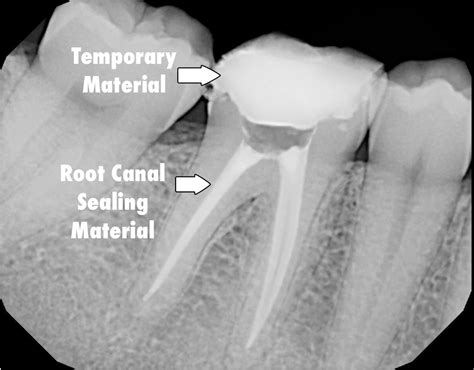

• Endodontic Procedures: In root canal treatments, Crown X Ray Dental technology aids in identifying the exact location and extent of the infection, ensuring that the procedure is performed accurately.